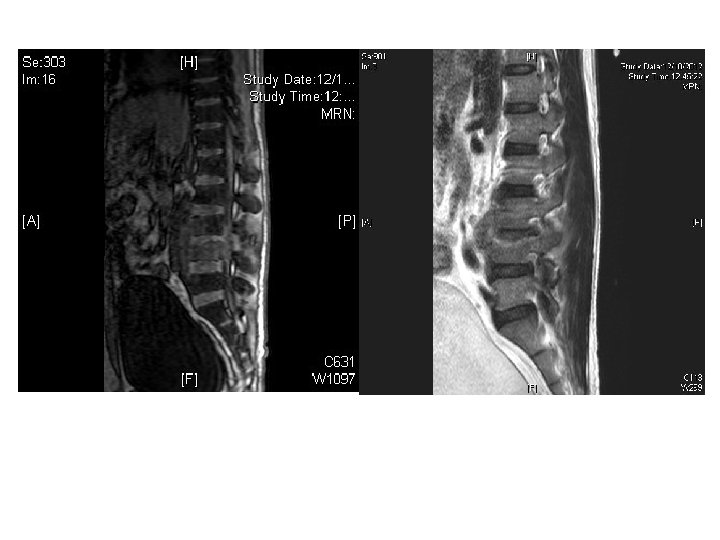

Case 4 • • • M/40 IVDA Personality disorder c/o LBP for 3 days

Case 4 • • • M/40 IVDA Personality disorder c/o LBP for 3 days No injury Could not walk

Questions • What were the red flags of LBP?

• What were the X ray findings? • What were the differential diagnosis?

• What were the X ray findings? • What were the differential diagnosis? • What other imaging Ix you would consider?

• How to manage this patient?